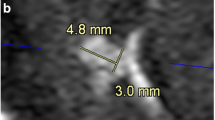

The inter-observer agreement for stenosis assessment was 0.956 (95% confidence interval 0.928, 0.973). Detailed comparisons between CS TOF-MRA and DSA for evaluating intracranial and cervical arterial stenosis are summarized in Table 1 and Supplementary Tables S3. The luminal stenosis ratios measured on CS TOF-MRA were higher than those measured on DSA, but significant differences were only found in mild stenosis (Supplementary Table S3). The luminal stenosis grade of CS TOF-MRA was concordant with that of DSA in 50 of 61 segments (82.0%, Table 1). No significant differences between the luminal stenosis grades assessed on CS TOF-MRA and DSA were found according to the Wilcoxon signed-rank test (p = 0.366). Of the remaining 11 segments, 7 segments were overestimated and 4 segments were underestimated. Detailed results of those segments are summarized in Table 2. A representative case is shown in Fig. 1. (Several mismatched cases are presented in Supplementary Figures S2 to S5.)

Compressed sensing time-of-flight MR angiography (CS TOF-MRA) and DSA in a 53-year-old patient. CS TOF-MRA shows a focal high-grade stenosis in the proximal M2 segment of the right middle cerebral artery with visible distal branches (a, hollow white arrow), and a focal high-grade stenosis in the proximal internal carotid artery (a, b; white arrow). DSA reveals almost identical features of stenosis (white hollow arrow in c, and white arrow in e) at the corresponding locations. Signal loss along the distal segment of the left vertebral artery is observed in CS TOF-MRA (a, white arrow head). DSA shows a left hypoplastic vertebral artery without any stenosis (d, white arrow head)